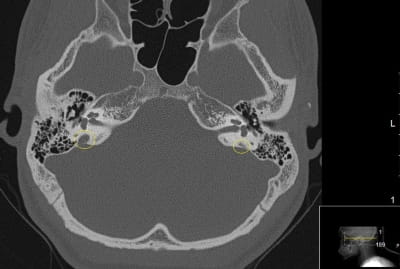

This CT scan shows a patient with an enlarged vestibular aqueduct (EVA) within the right inner ear (left on this image). Note the difference in size of the enlarged vestibular aqueduct circled in yellow on the left of the image, as compared with the normal vestibular aqueduct on the right.